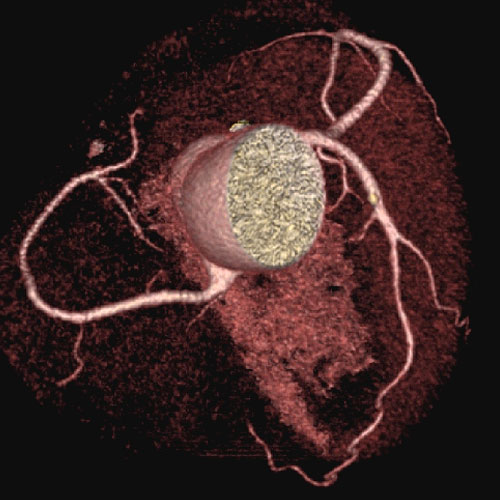

We utilize one of the few 64 slice CT scanners in North Texas that allows non-invasive diagnosis of such conditions as coronary artery disease (heart vessel blockage).  The heart vessels are displayed on our advanced 3D computer workstations where one of our doctors can make a diagnosis in minutes.  This procedure is much safer than cardiac catheterization.